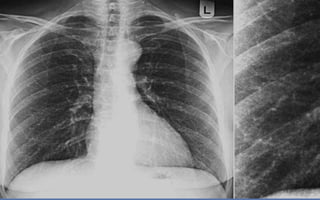

Radiografía de tórax

Patrón lobarBronconeumoníaNeumonía intersticialAbsceso pulmonarPatrón nodular

Southwick F. Pulmonary infections. In: Infectious diseases a clinical short course. LANGE. 2014